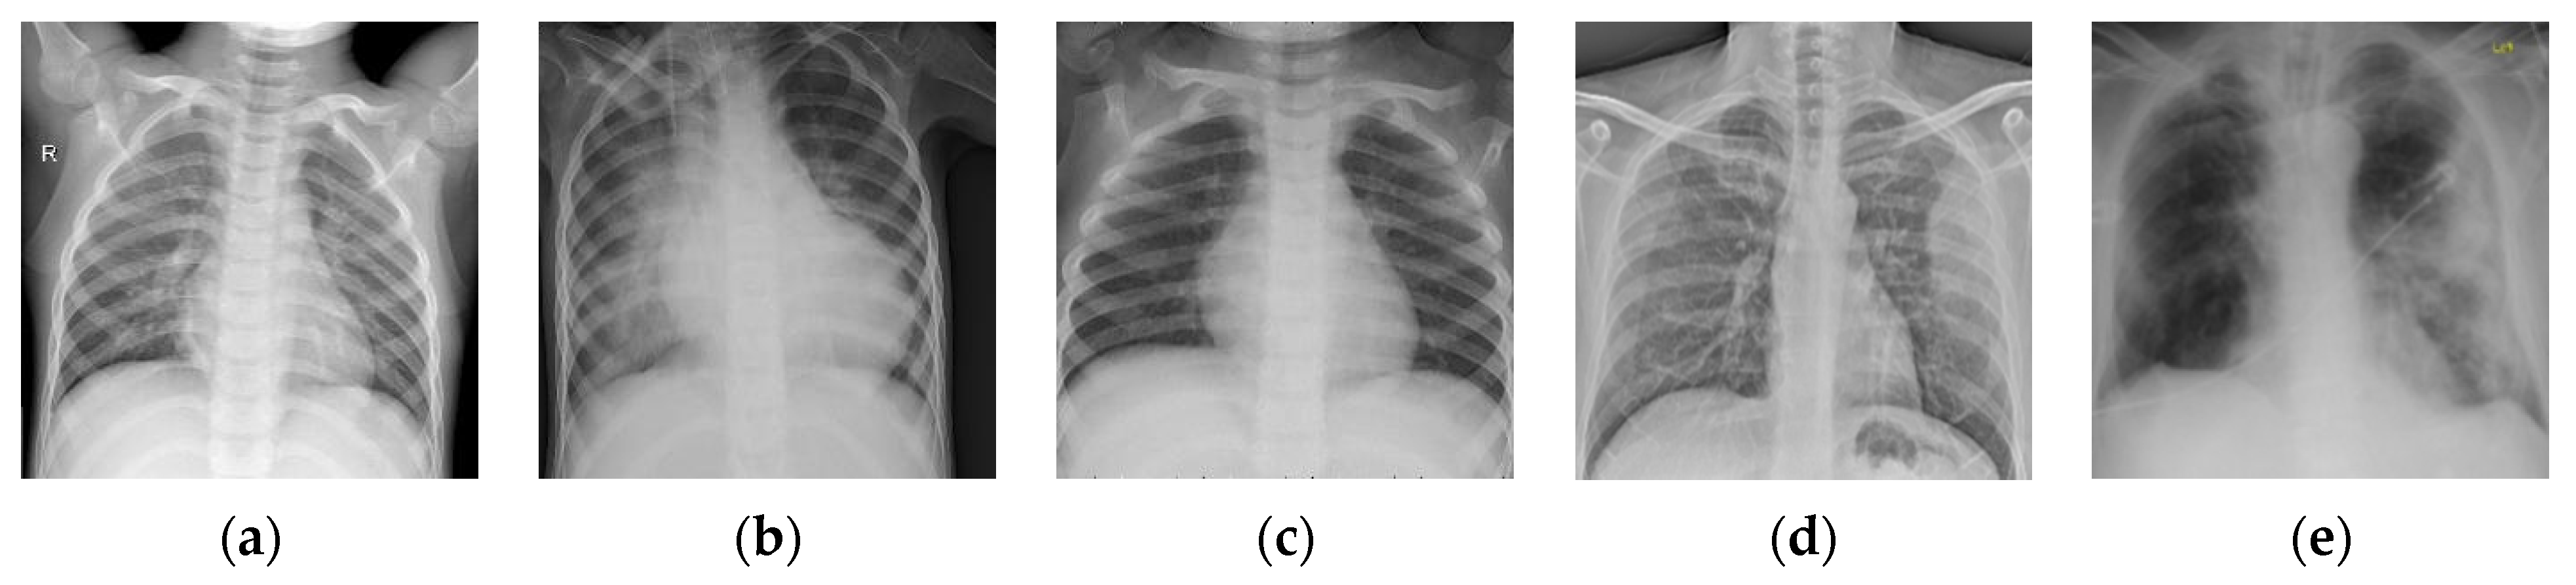

Figure 10.

Examples of the dataset Chest-2. (a–c) Normal; (d,e) pneumonia.

To further verify the consistency of the proposed BSTriplet loss, we have carried out comparative experiments on another dataset of chest X-ray images denoted as “Chest-2”. This dataset is also downloaded from the Kaggle [43] website. Here, Chest-2 is used for the classification of lung images into normal lung images and pneumonia images. Some examples are shown in Figure 10. The construction of Chest-2 is listed in Table 5. Each of the mentioned four light-weighted networks is trained with four kinds of losses on Chest-2. Similar to the experiments on Chest-1, all these images in Chest-2 are resized into . We have performed the K-means algorithm to partition the training images into six groups, and randomly selected six samples from each group to build the input batch for the proposed CE+BST loss.